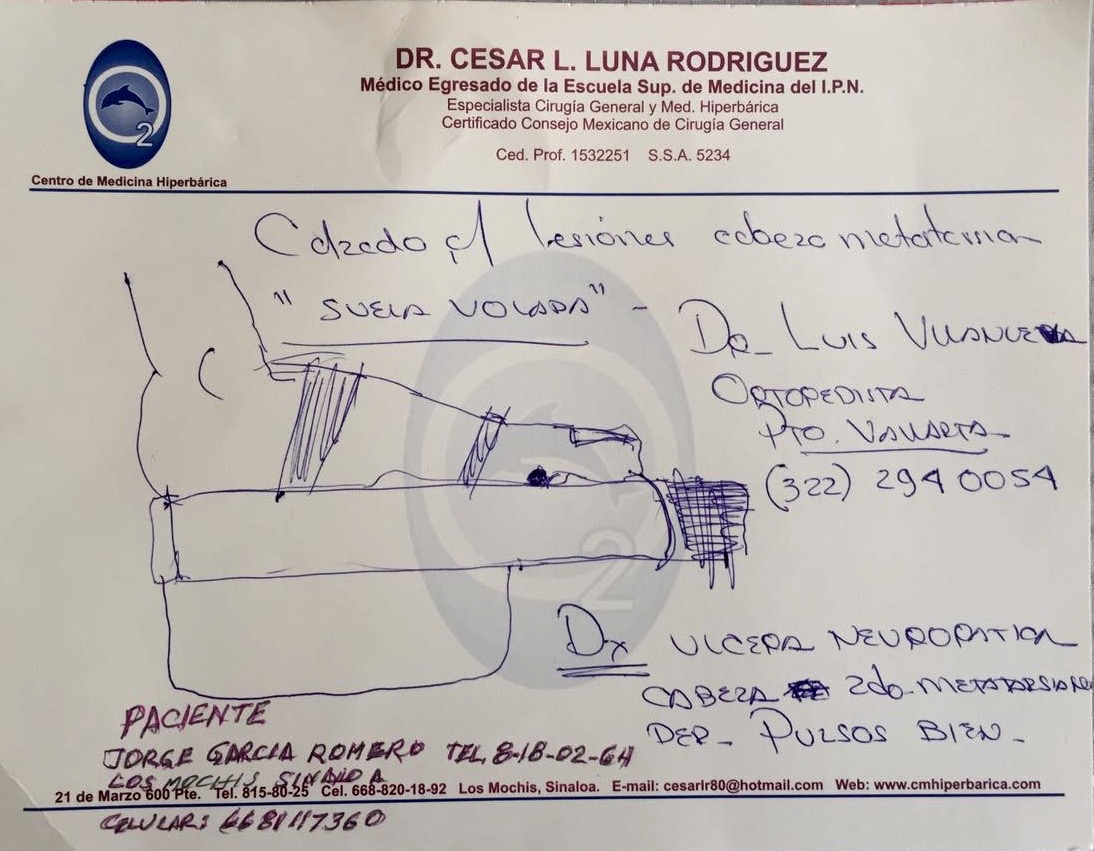

¿Qué le haría a este paciente?

Pie Diabetico en Riesgo Mecanico

- Evitar o Tratar

- Úlcera Neuropática

PULSOS (flujo)

Ulcera Neuropatica

Úlcera Neuropática 4to MT

Simple Osteotomía Percutánea